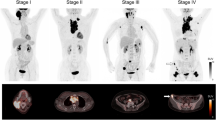

Improvement of anti-tumour vaccine efficacy assessment using FDG-PET monitoring

VAC and NI mice were sequentially followed for tumour development by PET at the five time points indicated in Fig. 5. When the first PET series was performed (day 34), all mice were still alive in both cohorts, but two NI mice displayed clinical signs suggesting tumour invasion at examination of the abdomen. PET images indicated lymphoma lesions in the two clinically suspect mice and in two additional NI mice (50% of the NI mice) with total calculated volumes of 1.35, 0.27, 0.11 and 0.10 cm3, respectively (mean 0.46 ± 0.60 cm3, Fig. 6a). The first two mice died with massive invasion before the scheduled PET image at day 47, while tumours from the latter grew to 5.50 and 5.00 cm3, respectively. Two additional mice died before next PET acquisition at day 55 and had newly developed bulky lesions at day 47 (2.86 and 2.93 cm3, respectively). A seventh mouse developed lymphoma later (detection of a 0.35 cm3 mass at day 55) also with a rapid evolution (not shown).

Tumour volume and SUVmax measured on PET images in vaccinated and control mice. a Record of tumour-free mice, dead mice and total tumour volume for tumour-bearing mice. The FDG-PET time course (days 34, 47 and 55) post-tumour challenge in NI (n = 8, black dots) and VAC mice (n = 7, white dots) is indicated. Lymphoma development was delayed in VAC mice (Student’s t test at day 47: P = 0.0034). b Maximum standard uptake values (SUVmax) as a function of tumour volume. All the data acquired on days 34, 47 and 55 are shown, i.e. the same mouse can be represented twice. SUVmax were significantly lower in VAC mice than in NI mice (Student’s t test: P = 0.0214)

In contrast, 100% of the VAC mice were free of tumour image at day 34 and 43% had still not developed lymphoma images at days 47, 55 and even later (Fig. 6a and data not shown). In the four VAC mice that escaped protection, the first lesions were detected at day 47 i.e. 13 days after first detection in NI mice. In good concordance with expectations, the day 47 tumour volumes were markedly lower in the VAC mice than in the live NI mice (0.68 ± 0.48 vs. 4.073 ± 0.6876 cm3, respectively, P = 0.0034). Moreover, the tumour activity, which could be quantified by SUVmax calculation, was consistently lower in VAC mice than in NI mice, whatever the tumour volume (3.37 ± 0.27 vs. 2.11 ± 0.19 respectively, P = 0.0214, Fig. 6b), demonstrating lower glucose metabolism in VAC mice tumours.

Overall, the results obtained by PET monitoring demonstrated that the difference in survival between the two mouse cohorts could be anticipated at day 34 and 47 by the number of abnormal FDG foci seen on images and by tumour volume and SUVmax calculation, which all indicated delayed lymphoma growth and metabolism in VAC mice.

The A20 cell line has been widely used for the in vivo testing of vaccination procedures against lymphoma [11–18]. In our study, we vaccinated mice by subcutaneous injections of A20 cell lysate mixed with conventional adjuvant prior to challenge by live A20 cells. This procedure is not applicable to human patients and was used as a model to induce an A20 tumour-specific immune response which was tested by an IFN-γ ELISPOT assay. Comparison of the natural evolution of the vaccinated (VAC) mice and control NI mice revealed significantly better survival of the VAC mice that correlated with a lower incidence and delayed development of lymphoma as visualized by FDG-PET. Most interestingly, FDG-PET allowed early discrimination of tumour growth between the VAC and NI mice. First, day 34 images showed that 50% of the mice had developed tumours in the NI group, whereas all the VAC mice were still tumour-free, suggesting a delay in tumour development in the latter. Second, analysis of the lesions revealed in PET images demonstrated significant differences in volume and SUVmax between the two groups (Fig. 6a, b). These differences revealed a reduced rate of tumour growth in the VAC group. Moreover, the lower SUVmax measured in all VAC mice tumours, irrespective of their volume, indicated that they displayed a decreased metabolic activity. Diminished cell viability or proliferation rate have been shown to limit FDG uptake [28, 29]. In VAC mice, the anti-tumour immune response may be responsible for both cell killing by necrosis or apoptosis and cell cycle arrest, a phenomenon known as dormancy [30].